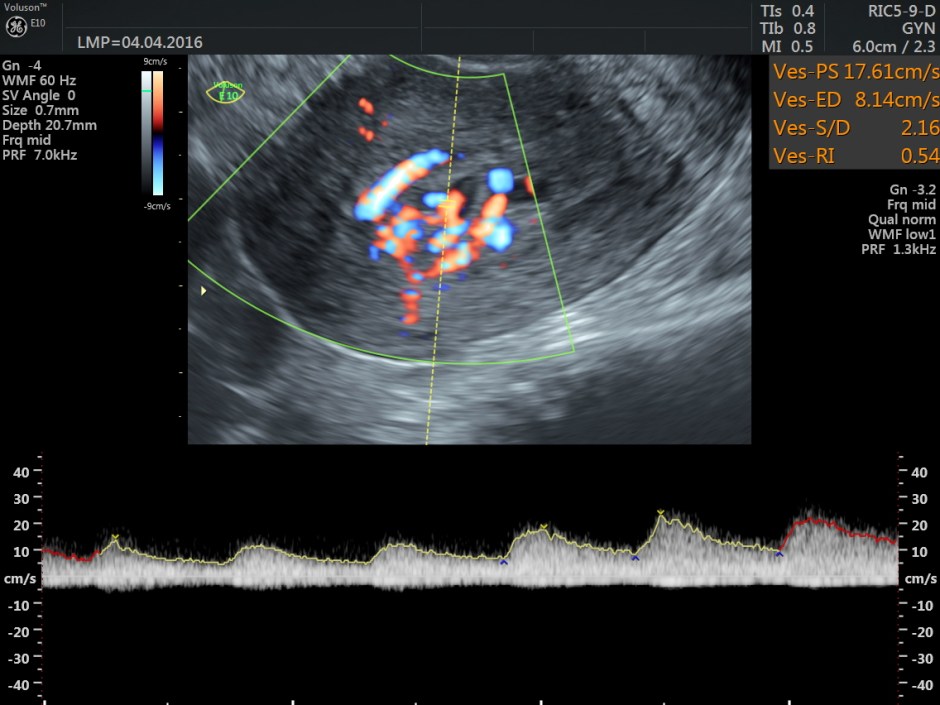

Spectral Doppler images show arterial flow with low resistance at different points .

Typically shows serpiginous/tubular anechoic structures within the myometrium with a low resistance (RI ~0.2-0.5), high velocity flow pattern on colour Doppler interrogation.